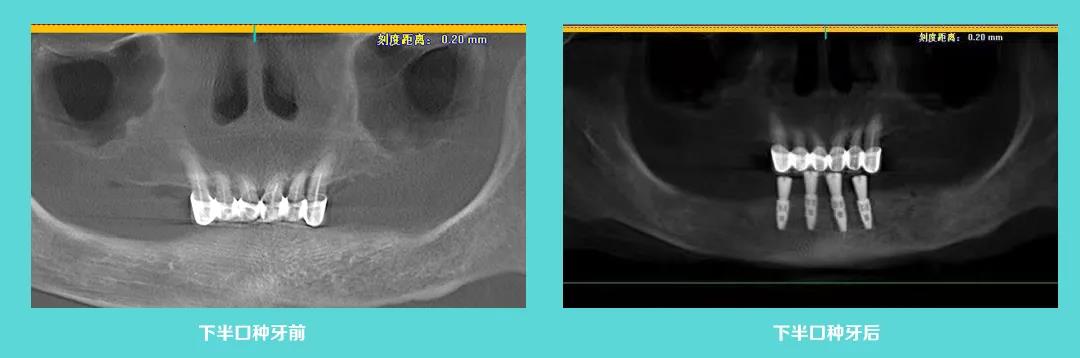

上图为数字化导板种植牙前后对比图,顾客原本骨头偏低,周围神经密集,利用数字化导板科学种牙,精准植入,避开神经,麦芽团队成功为一位七十多岁的老人种上新牙。麦芽数字化精准种牙,效果可预见,数字更精准,体验更舒服,稳定更持久。